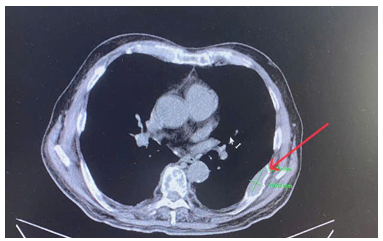

· CT lồng ngực:

Hình 1. Khối kích thước 17x19 mm, bờ tua gai, ngấm thuốc cản quang. Cả 2 trường phổi có giãn phế nang lan toả ở thuỳ trên phổi trái

Hình 2. Khối ngấm thuốc bên xương sườn VII bên trái kích thước 36 x 23 mm